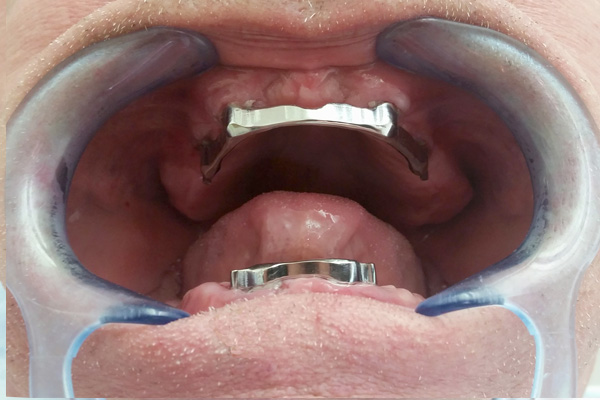

Overdenture

Overdentures are semi-fixed dentures are placed on dental implants. They are held in places in the jaw with precision attachments: either a sphere or a bar. Overdentures are can easily be removed for cleaning and they are held firmly in place while eating or speaking.